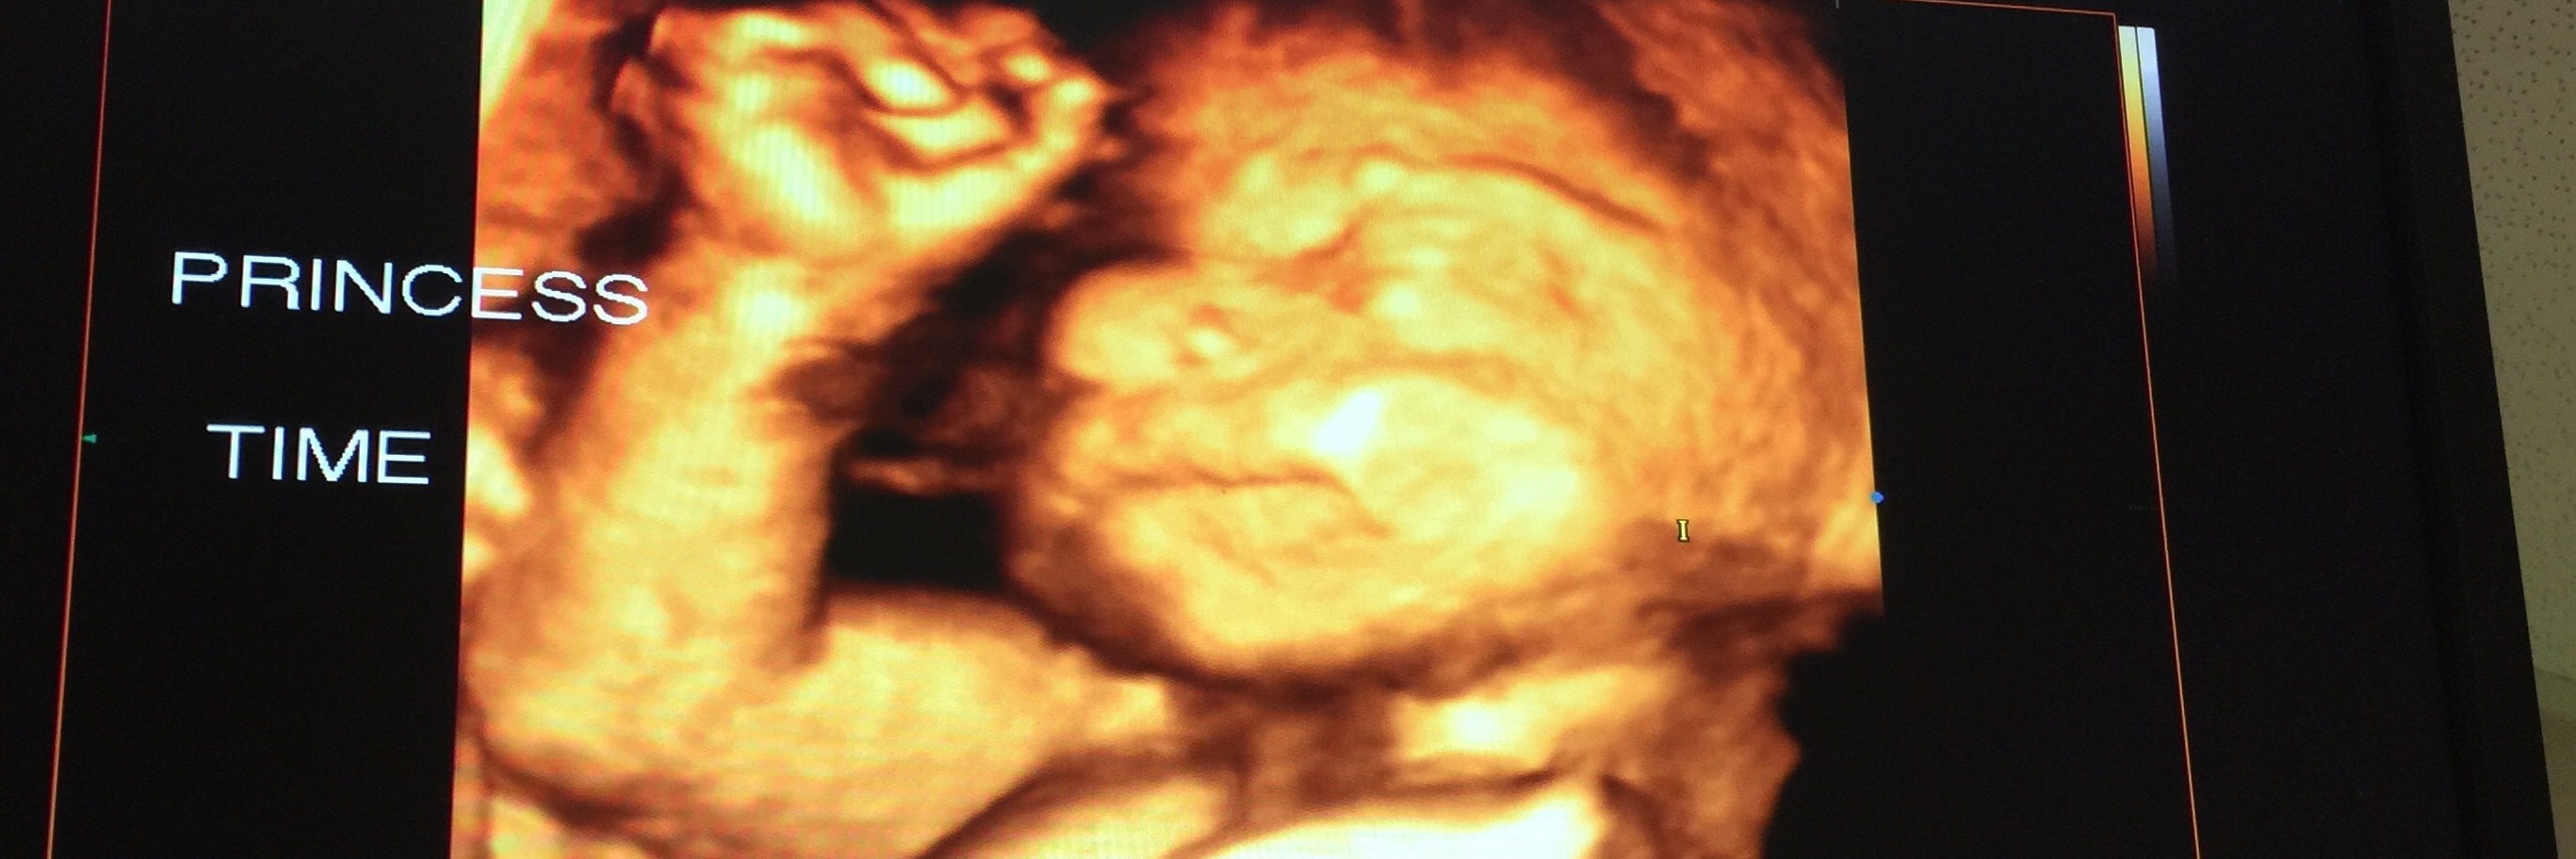

A few days ago my husband and I experienced one of life’s redefining moments — the ones that divide time into two parts: before and after. I had a fetal echocardiogram done and our unborn baby girl was diagnosed at 24 weeks with the congenital heart disease Tetralogy of Fallot (TOF).

The diagnosis shattered our world and our hearts. It was unexpected and the last thing on our radar. We were still ecstatic after recently finding out our baby was a little girl. We went from being on top of the world, to quite frankly the lowest point we’ve ever been at as a family. This pregnancy has been high-risk and complicated since week 20 when we learned our baby’s limbs were measuring two weeks behind where they should be in comparison to the rest of her body. Since then, it’s been test after agonizing test trying to pinpoint what — if anything — was wrong with our precious baby girl.

Her name is Nylah (NY-lah). We were saving her name to reveal at her birth, but decided to share it with you now so in your prayers you can speak her name, Nylah. We are praying very hard she will stay in my womb as long as possible because as our fetal cardiologist has said, a premature birth will only add to the complexity of Nylah’s fight once she is born.